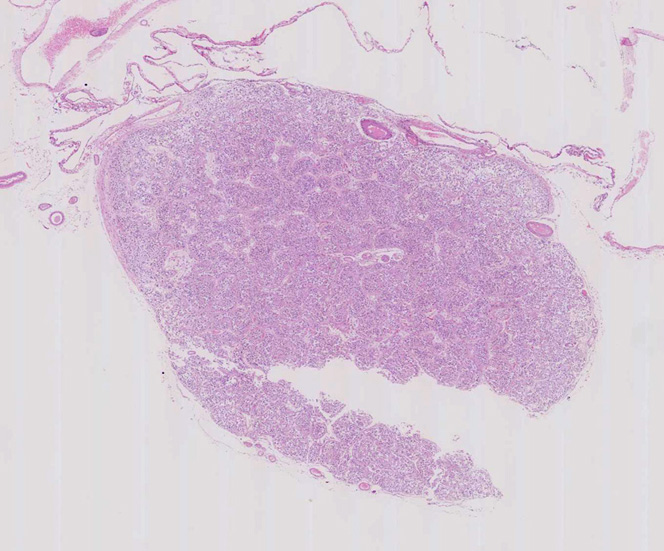

松果体の組織像

normal pineal gland tissue

pinealbodyloupe.jpg